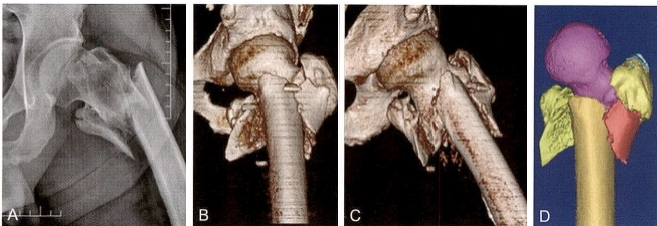

术毕透视,骨折复位质量优(4分),内固定稳定性优(7分)。术后 三维CT 证实仅前内下角获得骨皮质对骨皮质的可靠支撑。术后卧床2个 月,拍片发现前内侧角皮质愈合后开始扶双拐下地,1个月后扶单拐行 走。随访7个月,骨皮质愈合范围达到1/3周径,外侧壁也出现骨桥连接。 患者已去拐自由行走,功能良好(图9-22)。

图9-22 全转子区骨折。A.术前X线片,显示为31 A3型骨折;B 、C.术前三维CT示 骨折为全转子区骨折,分别有头颈骨块、股骨干骨块、小转子骨块、外侧壁骨块,前 壁骨块大转子分裂为前后2块;D~F. 采用mimics软件模拟骨折复位,显示骨折粉碎 程度

图9-22 ( 续 )G 、H. 闭合复位获得良好对线之后,微创导入钢丝,准备捆扎收拢小转 子骨块;I. 头髓钉手术之后,收紧小转子钢丝,但捆扎在髓内钉主杆上。为了避免干 扰骨折愈合,将其拆除;J 、K 、L. 术毕透视正位、侧位和前内侧斜位,示内芯螺钉拧 紧,远侧交锁螺钉打入在动力位;M 、N. 术后第5天拍片,示环周骨皮质缺损很多;O 、P. 术后三维 CT 显示仅前内下角约1/6的环周皮质相互抵住

图9-22 ( 续 )Q 、R.三维CT透明处理显示头髓钉内固定位置良好,髓内钉充满髓腔, 消除了髓内钉的摆动(雨刷效应);S 、T. 术后7个月,透视示股骨颈无短缩,内侧股 骨距愈合良好,外侧壁也出现骨桥连接。注意:与术后即刻相比,交锁螺钉上移